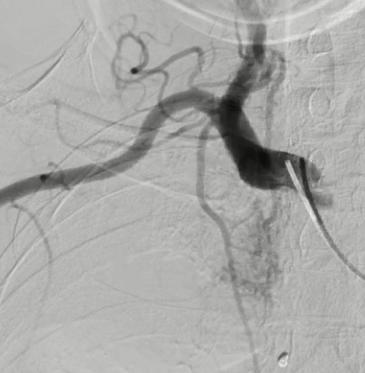

肺癌伴两肺转移,癌性淋巴管转移,体肺动脉化疗,支气管动脉联合肺动脉置管化疗。